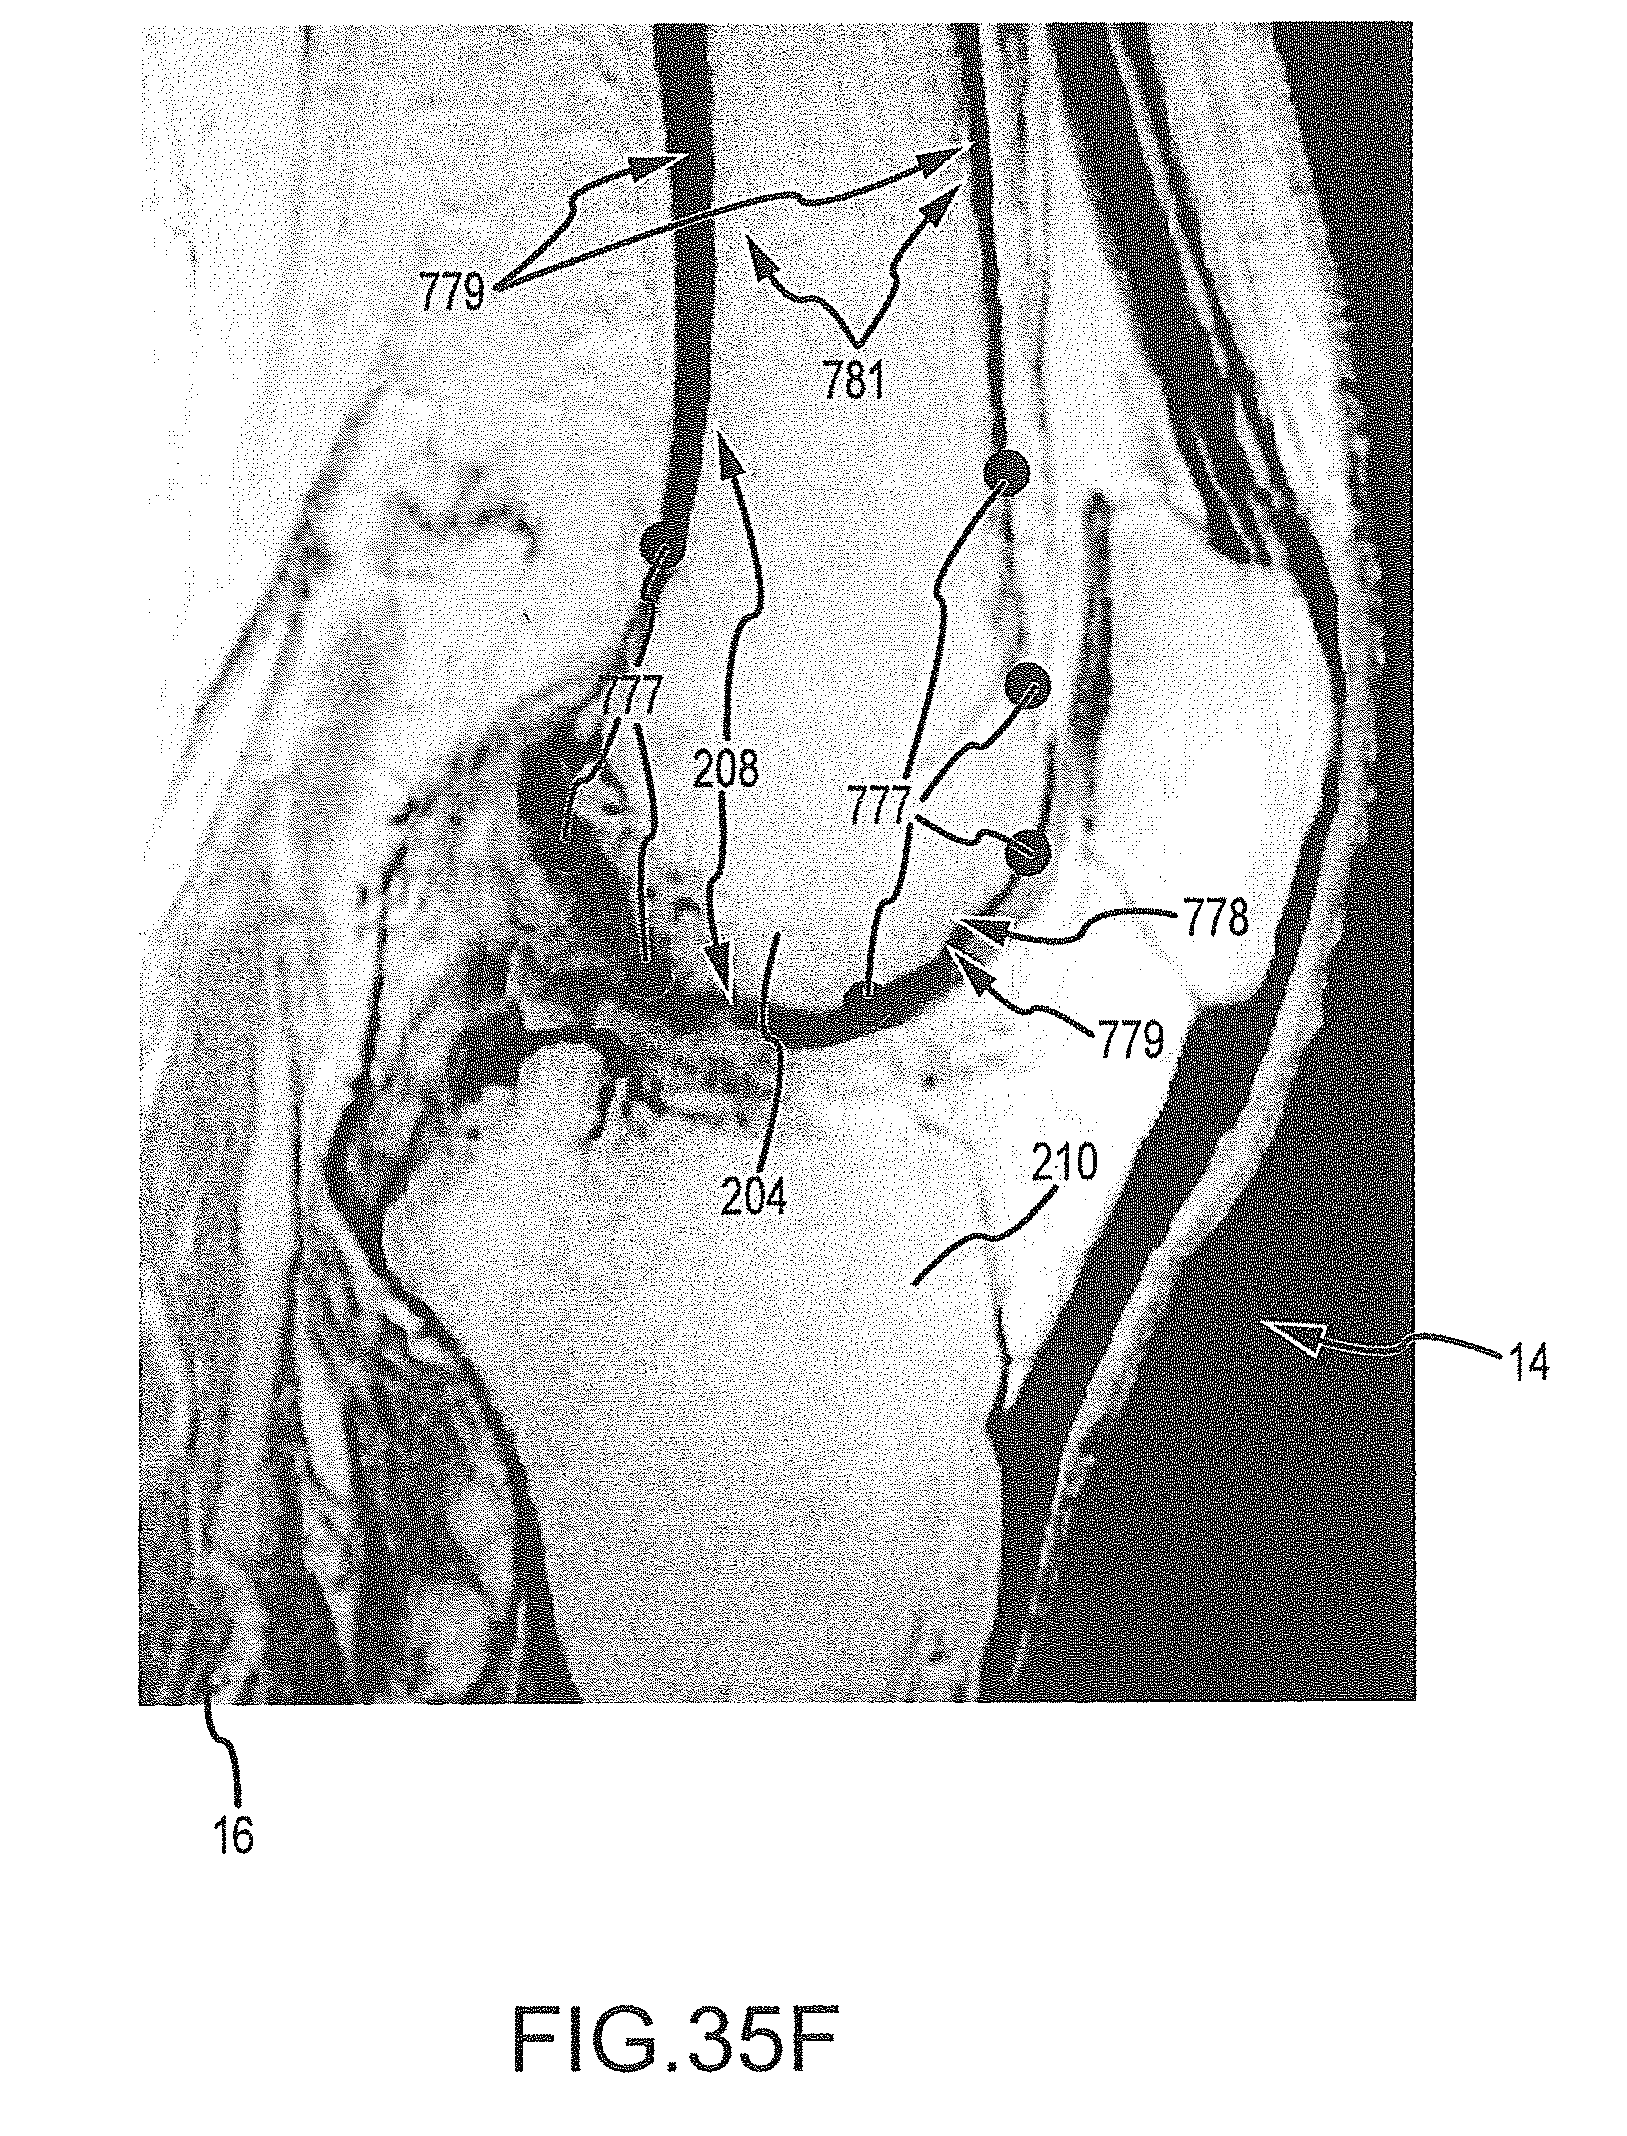

FIGS. 35A-35H are a series of sagittal image slices wherein landmarks have been placed according the process of FIG. 34.